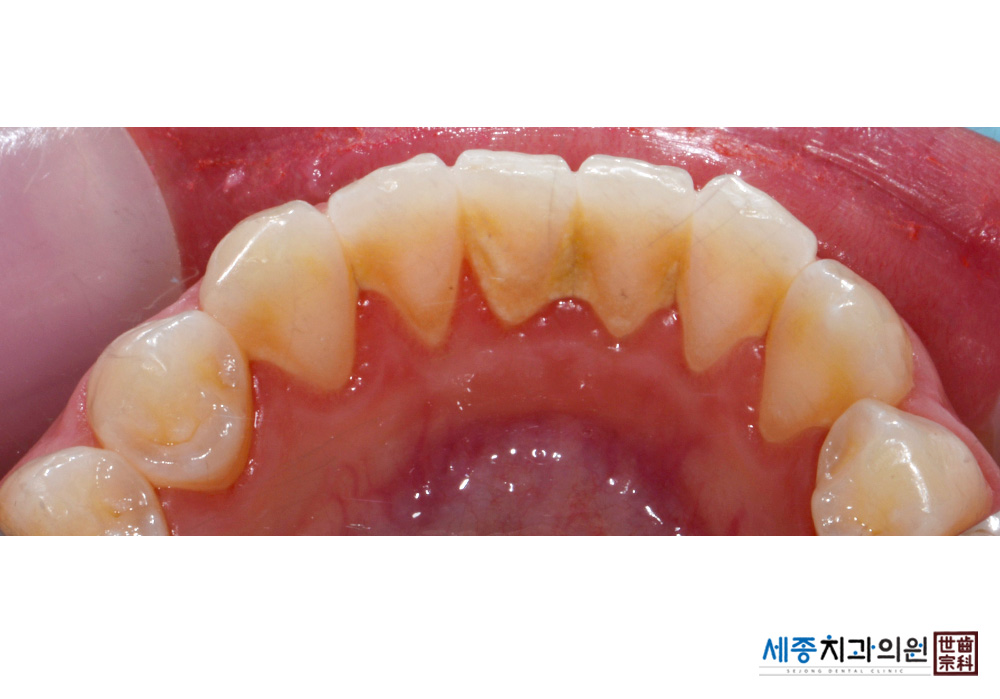

[스케일링] 치주질환 예방 스케일링 치료

치료전 : 2016-10-28

가글마취&저주파 스켈러를 사용한 스케일링